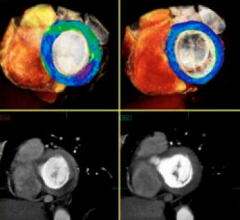

Feature | Dave Fornell

The key takeaway message from the Society of Cardiovascular Computed Tomography (SCCT) annual meeting in July was that…

The Society of Cardiovascular Computed Tomography (SCCT) annual meeting July 10-13 in San Diego covered the latest CT…